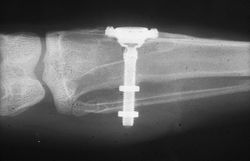

عام 1982 في تورنتو، قدم برانمارك عملاً كان قد بدأه منذ 15 عاماً في گوتنبورگ. اكتشافه وتطبيقه لاندماج العظام، أو الانصهار الحيوي للعظام إلى مواد خارجية، كانت وثائق لا مثيل لها ولم يسبق جمعها من قبل. حاز مؤتمر تورنتو على تقدير واسع النطاق لأساليب ومواد برانمارك لزراعة الأسنان ويعتبر واحداً من أعظم الاكتشافات العلمية في طب الأسنان منذ أواخر السبعينيات.[7]

اكتشاف اندماج العظام